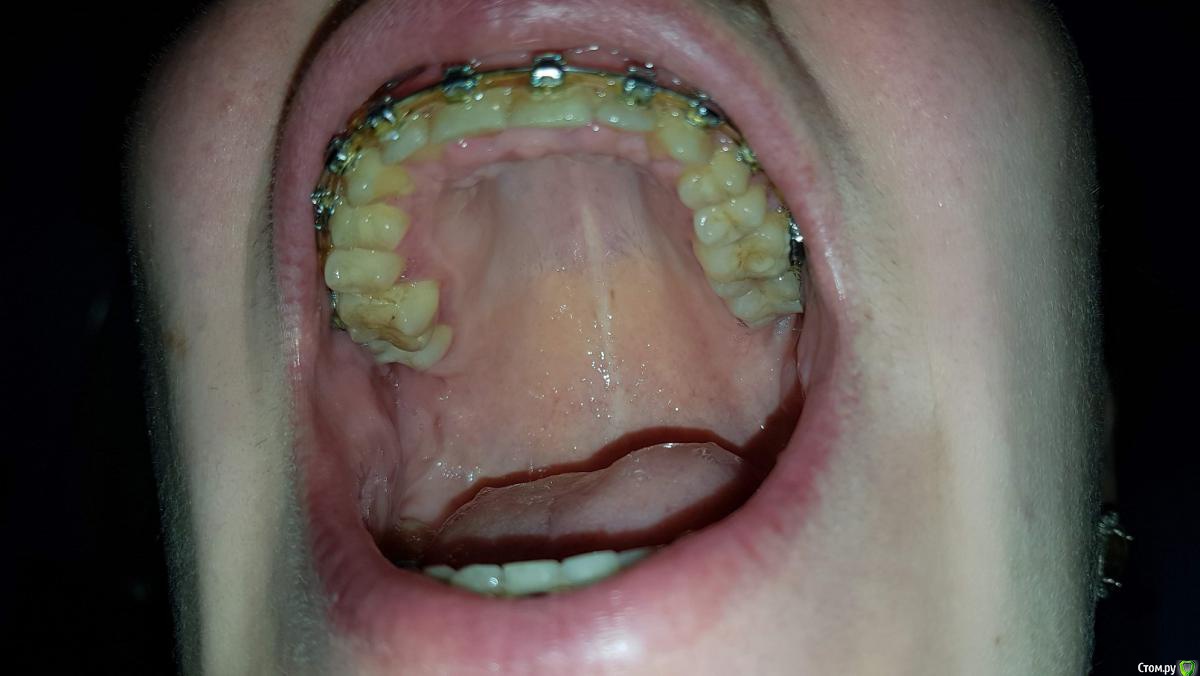

Жена начала носить брекеты в сентябре 2016 г. Цель выровнять зубы и убрать щелчки в области где суставы челюстные ( извините за термины, может и ошибаюсь) убрать щелчки при открывании рта широко.

Изначально предложили удалить сверху четверки верхние. Снизу 4 или 5 не выросло вообще (т.е. в нижнем ряду изначально не хватало 2 зубов). Сейчас после всех проделанных работ ортодонтом было предложено следующее:

удалить нижнюю восьмерку с правой стороны, с левой стороны восьмерка была удалена до начала лечения. и с левой стороны предложено раздвинуть зубы 6 и 4 (или 5 неизвестно какой там 4 или 5 в итоге вырос, а какой не вырос).

С правой стороны где большой промежуток без 2 зубов, там установлено уже 2 имплантата( сделано расщепление и установлено одномоментно два имплантата)

В итоге сейчас стоит вопрос расширять ли зубы слева снизу для еще одного имплантата и удалять 8 или же этого всего не делать, обратно стянуть и снимать брекеты.